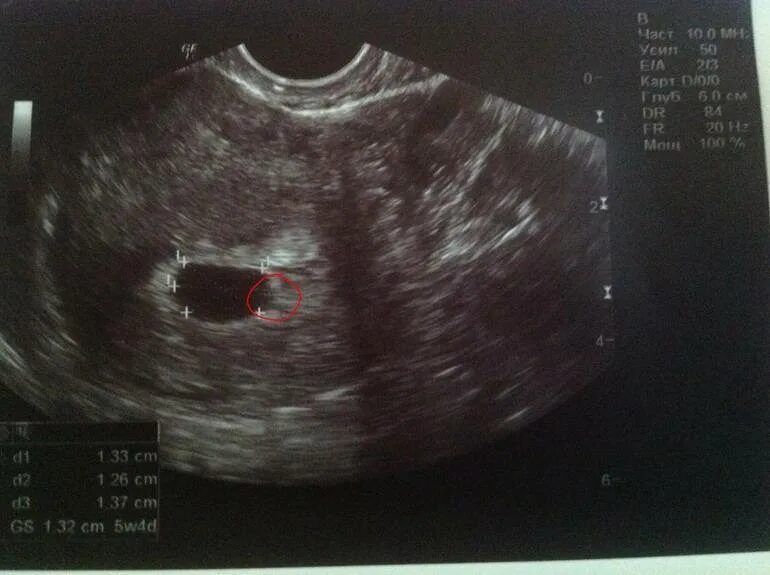

Плодное яйцо желточный мешочек